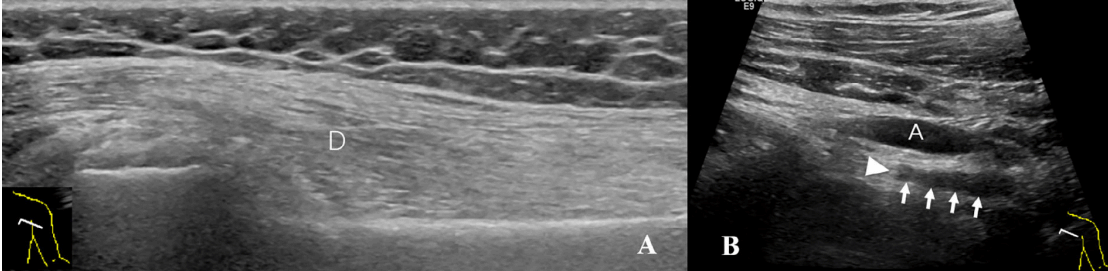

病例2:51岁女性在修复肩袖撕裂后出现右肩活动范围受限,持续2个月。A,左侧三角肌(D)正常。B,右侧三角肌(D)萎缩,回声增强。C,右侧腋神经(箭头)回声减低,弥漫性肿胀。D,彩色多普勒超声显示伴随的旋肱后动脉(A)和静脉(V)。

病例4:53岁女性左肩关节反复脱位,关节镜复位后左肩无力,持续3个月。A,三角肌(D)萎缩,回声增强。B,腋神经(箭头)位于腋动脉(A)的后方,神经的连续性中断(箭头)。